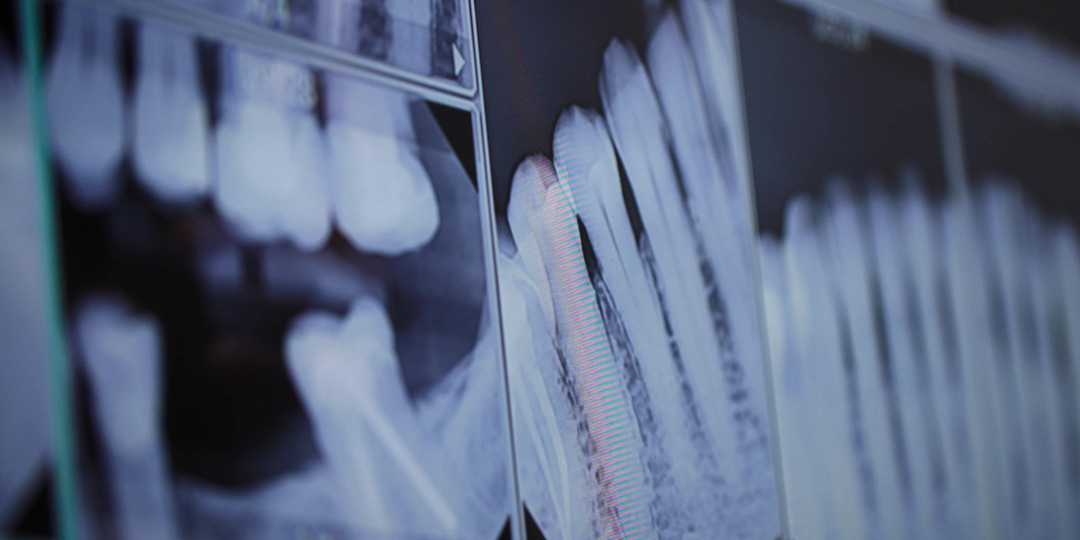

A dental implant can be used on its own to replace teeth or used in conjunction with either dentures or a dental bridge to provide added stability. Candidacy will be determined after a proper evaluation is performed by Dr. Marino. He’ll check the condition of not only your gums but your jawbone as well using an oral exam and other possible tests like digital X-rays.